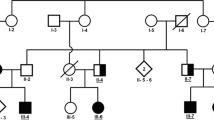

Families with inherited autosomal recessive forms of movement disorders were identified via personal contacts in Faisalabad and by visiting special education schools in Lahore. Criteria for the recruitment of the families included consanguinity and the presence of multiple individuals in each family with symptoms of spastic movement disorders. Patients in family RDHR07 were investigated first13, while those in the ANMD03 and RDFA06 families were newly recruited. A total of seven affected individuals were reported in family RDHR07 (Fig. 1A), five of whom were alive and presented movement disorders with intrafamilial differences. There were two patients each in families ANMD03 (Fig. 1B) and RDFA06 (Fig. 1C). The participants of the three families were videotaped by focusing on the upper and the lower limbs to record unusual movements. The sitting and standing positions were also videotaped. Voice, gait, neck position, eye blinking, and voluntary hand and foot movements were noted. The videos of the patients in family RDHR07 were analyzed previously13. Patients from families ANMD03 and RDFA06 were diagnosed by doctors at a local hospital. MRI analyses could not be performed for the patients in the three families. Blood samples were collected from all available family members in the three pedigrees. Genomic DNA was extracted using sucrose lysis and salting out from whole-blood samples.

Pedigrees and partial electropherograms. (A) Pedigree of family RDHR07. Patients were from multiple generations of the family. Filled black symbols denote those individuals with spastic paraplegia while the half filled symbols indicate those with a spastic /ataxic/dystonic disorder which is different from that of the other patients. The SPG11 allele genotypes of the participants are indicated under their symbols (+ = wild-type allele, − = deletion allele). (B) Pedigree of family ANMD03. Individuals who participated in the study are indicated. The DDHD2 genotypes are shown below the symbols for individual participants. (C) Pedigree of family RDFA06, with individuals affected in two branches. The AP4B1 genotypes of all the participating individuals are mentioned. (D) Partial electropherogram from BTSeq sequencing results of the SPG11 deletion allele NC000015.9:g.44894055_44902826del. The reverse complement sequence shows intron 20 (at left and base pairs written in bold) continuous with the sequence within intron 18 (at right and base pairs are not written in bold). The arrow indicates the start of intron 20, reading from right to left. Sequence is reverse complement with respect to the cDNA. (E) Partial electropherograms of DDHD2. Traces from healthy individuals with a wild-type sequence and patients with the variant c.985C > T are shown. The arrow indicates the changed nucleotide. (F) Electropherogram of AP4B1 showing the sequences of the carrier and the affected individuals. The start of the variant c.965-967delACTinsC is indicated by an arrow above the first of the changed nucleotides. The wild-type genomic sequence is shown under the trace of the affected individual, and the deleted/inserted nucleotides are written in lowercase letters and boxed. Sequence is reverse complement with respect to the cDNA.

At the time of recruitment, all patients in family RDHR07 were hypothesized to have the same genetic cause of their phenotypes due to their common ancestry (Fig. 1), despite slightly different clinical presentations of the five affected individuals (Table 1). The symptoms indicated complex movement disorders/dystonia/hereditary spastic paraplegia (HSP) with an onset of disease beginning at the age of 3–6 years. Patients IV:9 and IV:10 exhibited severe spasticity of all extremities and could walk only with support and a wide-gait. Other symptoms included dystonic posturing, hypomimia, spontaneous clonus associated with tremors and impaired positional sense. The instinctive Babinski sign on the right was observed for patient IV:9, and the Babinski sign was positive bilaterally for patient IV:10. Patient V:5 had generalized dystonia, including lower face dystonia with dystonic grimacing, cervical dystonia, dystonic postures of the upper and lower extremities and a dystonic gait. Patients IV:4 and V:7 however presented additional clinical manifestations (Table 1). Evaluation of patient IV:4 showed a wide-based spastic-ataxic gait along with a partial decline in the motor function of the right arm, truncal ataxia while sitting, leg pronounced spasticity and proximal weakness. Patient V:7 had an undetermined dystonic phenotype associated with moderate lower limb weakness, right foot inversion and left leg muscle atrophy.

PCR analyses performed in duplicate with the deletion-specific and wild-type-specific set of primers revealed that individuals III:10, III:11 and IV:2 were carriers of the deletion variant; patients IV:9, IV:10 and V:5 were homozygous for the deletion; and individuals IV:4, IV:5, IV:6, IV:11 and V:7 had only the wild-type allele (Fig. 1A, Supplementary Fig. 4). Patients IV:4 and V:7, though displaying some symptoms including spasticity or dystonia similar to their affected cousins (Table 1) did not have the SPG11 deletion allele, thus demonstrating intrafamilial genetic heterogeneity and indicating a separate cause of their phenotype.

For family ANMD03, exome sequencing data revealed 18 homozygous variants after applying the filtration criteria (Supplementary Table 4). Variants in most of these genes were either predicted benign or were not correlated to the patients’ conditions (Supplementary Table 4). However, the nonsense variant in DDHD2 (NM_015214.3) c.985C > T;p.(Arg329Ter) was prioritized (Table 2) because it was already known to cause spastic paraplegia (ClinVar VCV000452548.6)19. This DDHD2 variant segregated with the disease phenotype (Fig. 1E).

Finally, for family RDFA06, variant prioritization left 30 rare homozygous or hemizygous gene variants, including frameshift, missense and synonymous changes (Supplementary Table 5). The number of prioritized variants was further reduced to one by discarding those that affected amino acids not conserved in the vertebrates or for which the changes were predicted to be benign by multiple software programs (Supplementary Table 5). A frameshift insertion‒deletion in AP4B1 (NM_001253852.3), c.965-967delACTinsC;p.(Tyr322SerfsTer14), was the most likely variant (Table 2) that could account for the phenotype and segregated with the disease (Fig. 1F). The parents and the unaffected siblings were heterozygous, and the patients were homozygous for the variant.